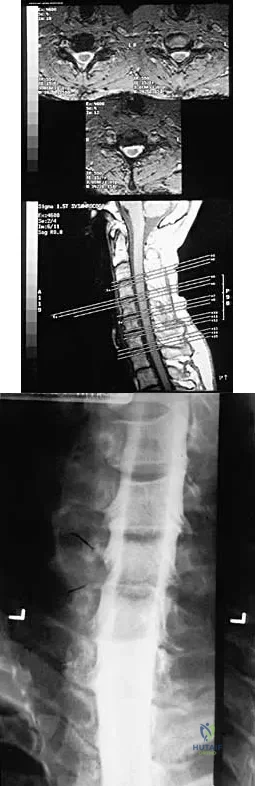

A patient with rheumatoid arthritis has an unstable pseudarthrosis after undergoing C1-2 posterior fusion. No neurologic deficits are noted, and repair with posterior transarticular fixation screws and a posterior wiring technique at C1-2 is planned. Which of the following preoperative studies offers the best visualization?

Options:

- Lateral flexion-extension radiographs centered over C1-2

- Cervical MRI

- Thin-cut CT through the C1-2 and C2-3 segments

- Vertebral artery angiography

- Electromyography of the cervical roots and spinal cord

Correct Answer: Thin-cut CT through the C1-2 and C2-3 segments

Explanation:

Dickman and associates reported a greater than 10% incidence of vertebral artery anomalies at the C1-2 junction that would preclude the use of either unilateral or bilateral transarticular screw placement. They noted that 13 of 105 patients had a high-riding transverse foramen that precluded bilateral screw placement. In another series, 17 of 94 patients had unilateral high-riding transverse foramina and three had bilateral anomalies. Thin-cut CT with sagittal reconstructions offers the best visualization of the anomalous position of the vertebral artery. They noted that single screw placement in combination with posterior C1-2 fusion was an effective means to secure C1-2 stability. MRI gives excellent visualization of soft tissues and spinal cord compression but is not as clear as thin-cut CT for visualization of the vertebral artery foramina. Vertebral artery angiography is an invasive study with an inherent potential for complications. Electromyography does not correlate with vertebral artery anatomy. Paramore CG, Dickman CA, Sonntag VK: The anatomic suitability of the C1-2 complex for transarticular screw fixation. J Neurosurg 1996;85:221-224. Dickman CA, Sonntag VK: Posterior C1-C2 transarticular screw fixation for atlantoaxial arthrodesis. Neurosurgery 1998;43:275-280.